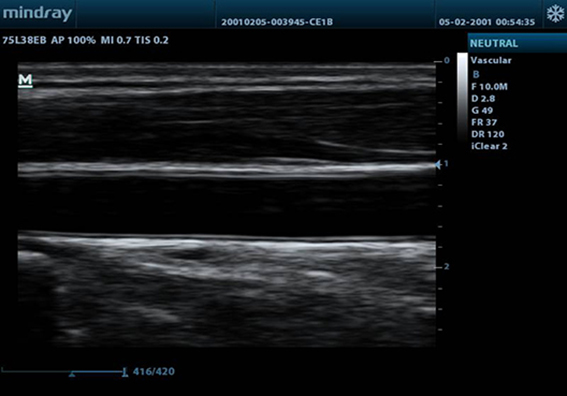

- iClear for Speckle Reduction Imaging, providing clear and sharp lesion contours.

- Sharper & Continuous Edges

- Smooth Uniform Tissues

- Cleaner ‘no echo areas